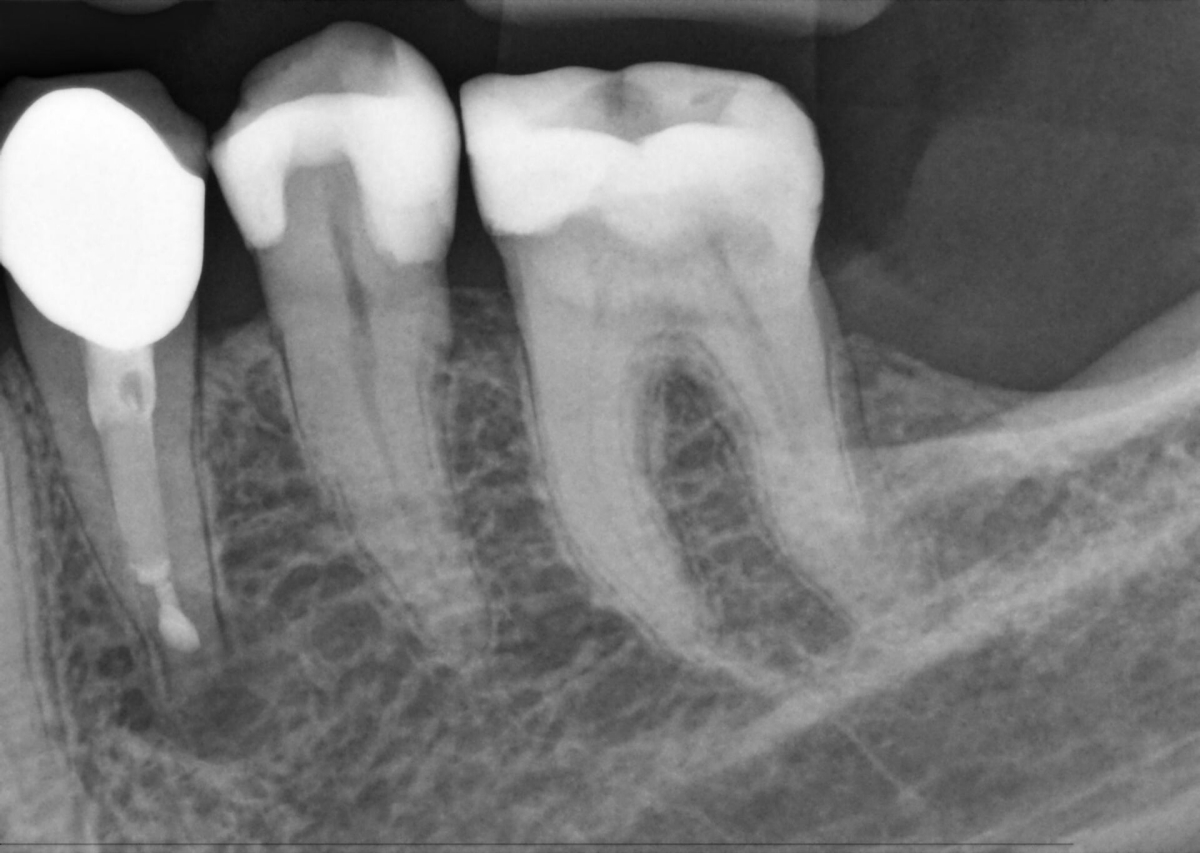

Direct Conversion Sensor (DCS): Sharp Image Details

The Direct Conversion Sensor (DCS) has revolutionized the standard of panoramic imaging. X-rays are directly converted into electrical signals. Thus, there is no signal loss due to light conversion as with conventional systems. The result: images with an extremely high and high-contrast level of sharpness - even at a very low dose. For clear diagnoses and even more targeted treatment.

The image shows an X-ray image with and without DCS technology. Move the control over the image and see for yourself the difference the DCS sensor makes to the image quality.